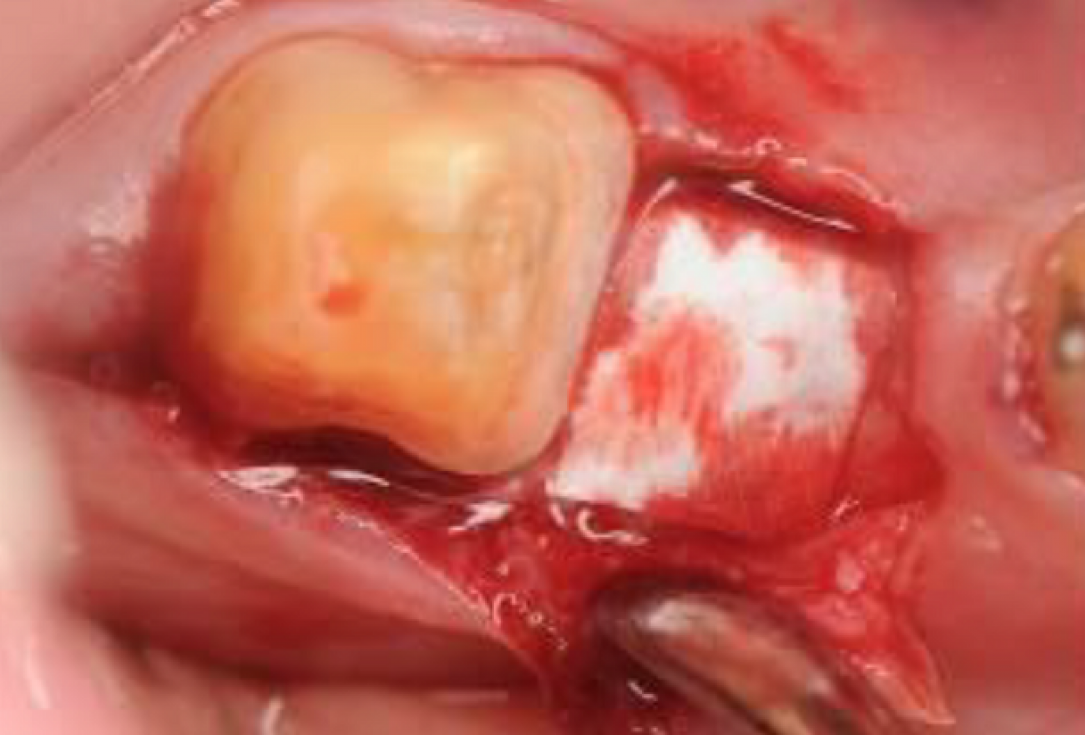

04/06 - Defect filled with small cerabone® granules.Intrabony defect treated using Straumann® Emdogain®, cerabone® and Jason® membrane - Dr. D. B. Hangyási